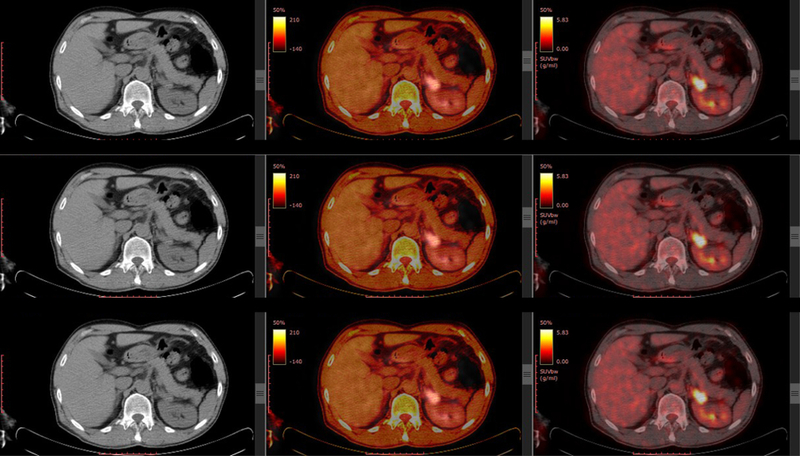

Narayana Health is launching a new advanced PET CT Scan facility for Cancer care. Positron emission tomography (PET) uses small amounts of radioactive materials called radiotracers, a special camera and a computer to help evaluate your organ and tissue functions. By identifying body changes at the cellular level, PET may detect the early onset of disease before it is evident on other imaging tests.

PET scans are performed on instruments that are combined PET and CT scanners. The combined PET/CT scans provide images that pinpoint the anatomic location of abnormal metabolic activity within the body. The combined scans have been shown to provide more accurate diagnoses than the two scans performed separately. Doctors can make more accurate diagnoses, develop more targeted treatment monitoring, which should result in improved patient outcomes.